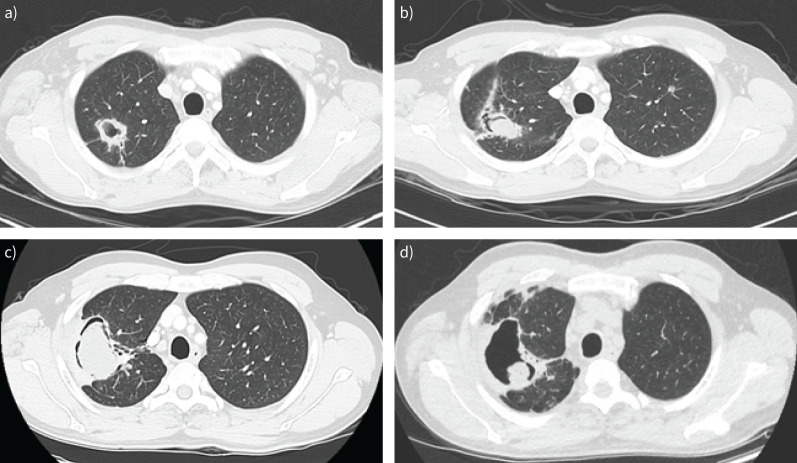

Chronic pulmonary aspergillosis has a range of manifestations from indolent nodules to semi-invasive infection. Patients may be asymptomatic or have chronic symptoms such as cough and weight loss or present with life-threatening haemoptysis. The physician can choose from a range of available therapies including medical therapy with antifungals, minimally invasive therapy with intracavitary antifungal therapy and surgery involving open thoracotomy or video-assisted thoracoscopic surgery. The patients with the most severe forms of pulmonary infection may not be surgical candidates due to their underlying pulmonary condition. The management of haemoptysis can include tranexamic acid, bronchial artery embolisation, antifungals or surgery. There are few controlled studies to inform clinicians managing complex cases, so a multidisciplinary approach may be helpful.